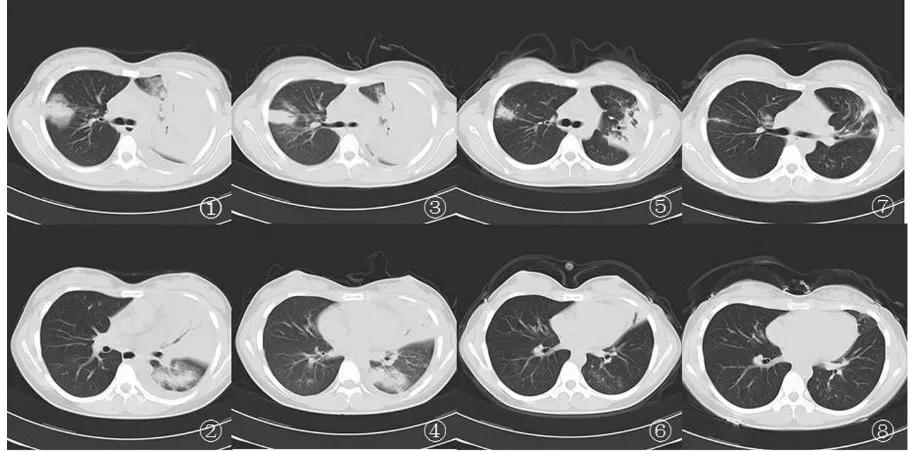

军团菌肺炎胸部影像相对特异性的表现是磨玻璃影中混杂着边缘相对清晰的实变影。虽然临床症状改善,影像学在短时间内仍有进展(1周内),或肺部浸润影几周甚至几个月后才完全吸收也是军团菌肺炎的影像学特点 [3] 。

图1①-⑧

注:①②患者入院第1天胸部CT示双肺多发斑片样渗出影,左上肺实变,内可见支气管充气征,伴有左侧少量胸腔积液;③④治疗1周后右上叶渗出影略有减小,左侧胸腔积液减少(胸穿术后);⑤⑥治疗6周后双肺渗出影明显吸收好转;⑦⑧双肺渗出影基本吸收,左上肺叶遗留纤维索条影和坏死物质排出后形成的空腔 [4] 。